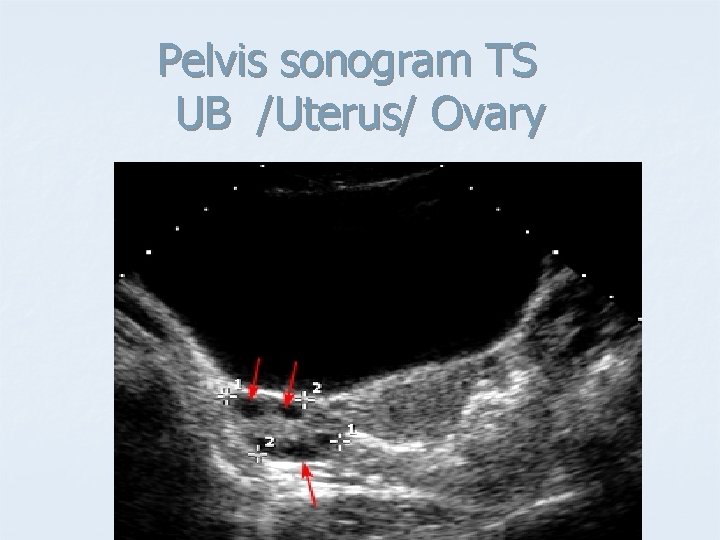

Pelvis sonogram TS UB /Uterus/ Ovary